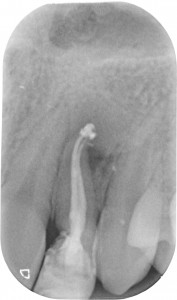

Ora Maddalena, così si chiama la ragazzina di questo dens in dente, con un piccolo allungamento di corona clinica seguito da limatura del margine incisale e una semplice otturazione di 12 e una corona in disilicato preparata su questo dens in dente, può tornare a sorridere. Ecco la foto e la rx a sei mesi dal caso finito. Tutto perfetto! Il 22 sta guarendo e le gengive e i denti stanno alla grande! Il brillantino invece ha perso il diamantino! ?